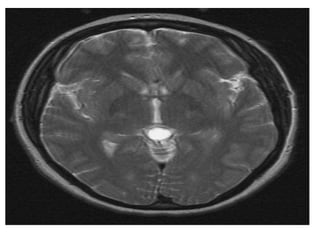

-MRI :

-Typically the tumors demonstrate expansion of the

tectal plate by a solid nodule of tissue

*T1 :

-Iso to slightly hypointense to grey matter

*T2 :

-Hyperintense to grey matter

*T1+C :

-Usually no enhancement

-Higher grade tumors tend to be larger and tend to

enhance more vividly

T1

T2 FLAIR shows a tectal mass leading to obliteration of the

cerebral aqueduct

T1+C shows a slightly hypointense tectal mass which does not

enhance , the mass obstructs the aqueduct and is stable over

8 years

T2 FLAIR showsa tectal mass leading to obliteration of the cerebral aqueduct

T1+C shows aslightly hypointense tectal mass which does not enhance , the mass obstructs the aqueduct and is stable over 8 years